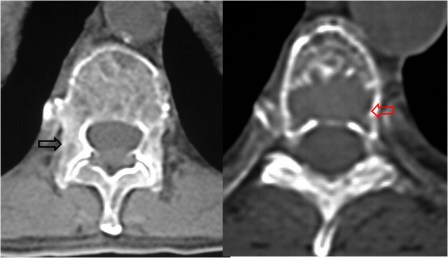

SIGNO DE LA DOBLE LÍNEA

Signo de osteonecrosis avascular visible en la resonancia magnética, en imágenes potenciadas en T2. En la osteonecrosis avascular se ve una línea de alta intensidad de señal rodeada por un anillo paralelo de hiposeñal, con frecuencia de bordes serpiginosos. La línea hiperintensa (flecha negra) corresponde a tejido de granulación hiperémico y la línea externa hipointensa (flecha roja) corresponde a hueso escleroso.

Otro ejemplo en un paciente con infartos óseos múltiples en fémur distal y tibia proximal.